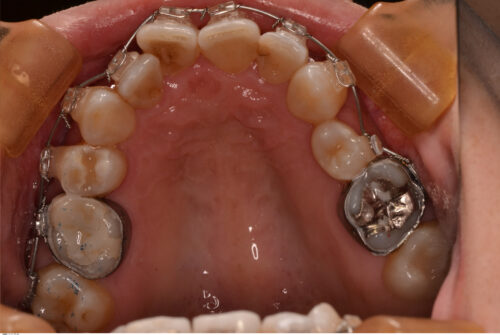

第2小臼歯は全て先天性欠損で下顎にはブリッジが入っています。

上顎は骨が硬くないので容易に移動しますが